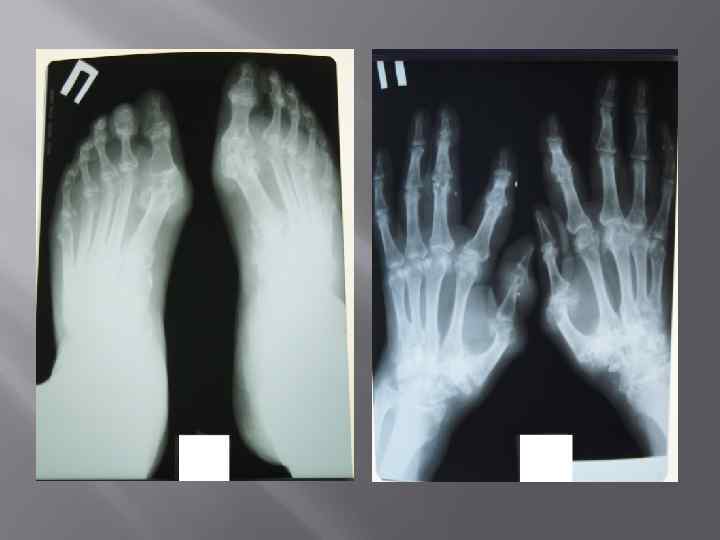

Жалобы На боли в области коленных суставов, их припухлость, боли в плечевых суставах, ограничение подвижности в них, боли в области локтевых суставов, ограничение сжатия пальцев кистей в кулак, множественные узловые образования в области суставов кистей, скованность и боли в пояснице.

Объективно: • У пациента наблюдается дефигурация 1 плюснефаланговоговых суставов. Дефигурация левого коленного и левого локтевого суставов. Объем пассивных и активных движений в коленном суставе снижен , сгибание составляет 60 градусов, разгибание до угла 10 градусов. Объем движений в голеностопных суставах снижен и составляет 0/10 гр. Определяются тофусы в области пястно-фаланговых суставов обеих кистей, локтевых суставов, болезненность при пальпации, ограничение в объеме движений в шейном, грудном и поясничном отделах позвоночника, грудной кифоз, сглаженный поясничный лордоз, положительные симптомы сакроилеита с обеих сторон.

КЛИНИЧЕСКИЙ ДИАГНОЗ: Подагра хронического течения: рецидивирующий подагрический полиартрит (тофусы), в сочетание с анкилозирующим спондилоартритом аксиальной формы высокой степени активности, поздняя стадия, рентгенологическая стадия 4. ФК III. ХБП, 3 стадии, хронический тубоинтерстициальный нефрит с исходом в нефросклероз ( подагрическая нефропатия ), кисты почек (р СКФ CKD EPI 35 мл/мин/1. 73 м 2). Гипертоническая болезнь 2 стадия, риск 3.